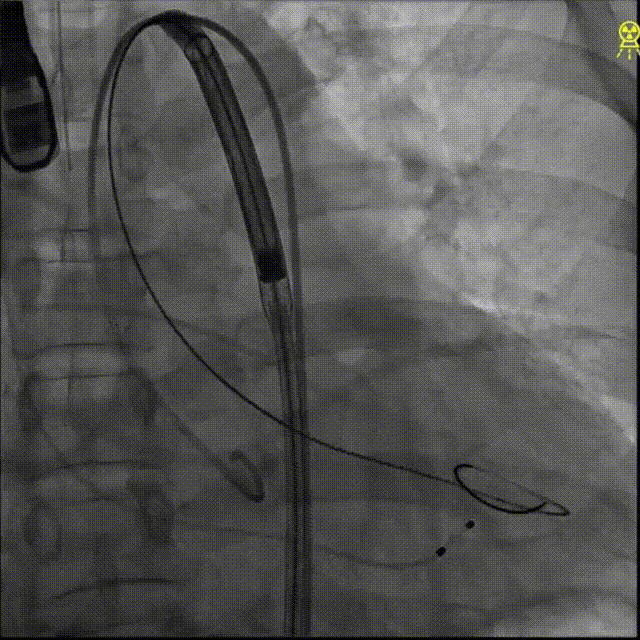

过弓及commissural alignment

定位及初始释放

初始释放开始后微调深度

120BPM下快速释放

双体位评估:释放角度及瓣膜低端平齐(LAO)

最终释放